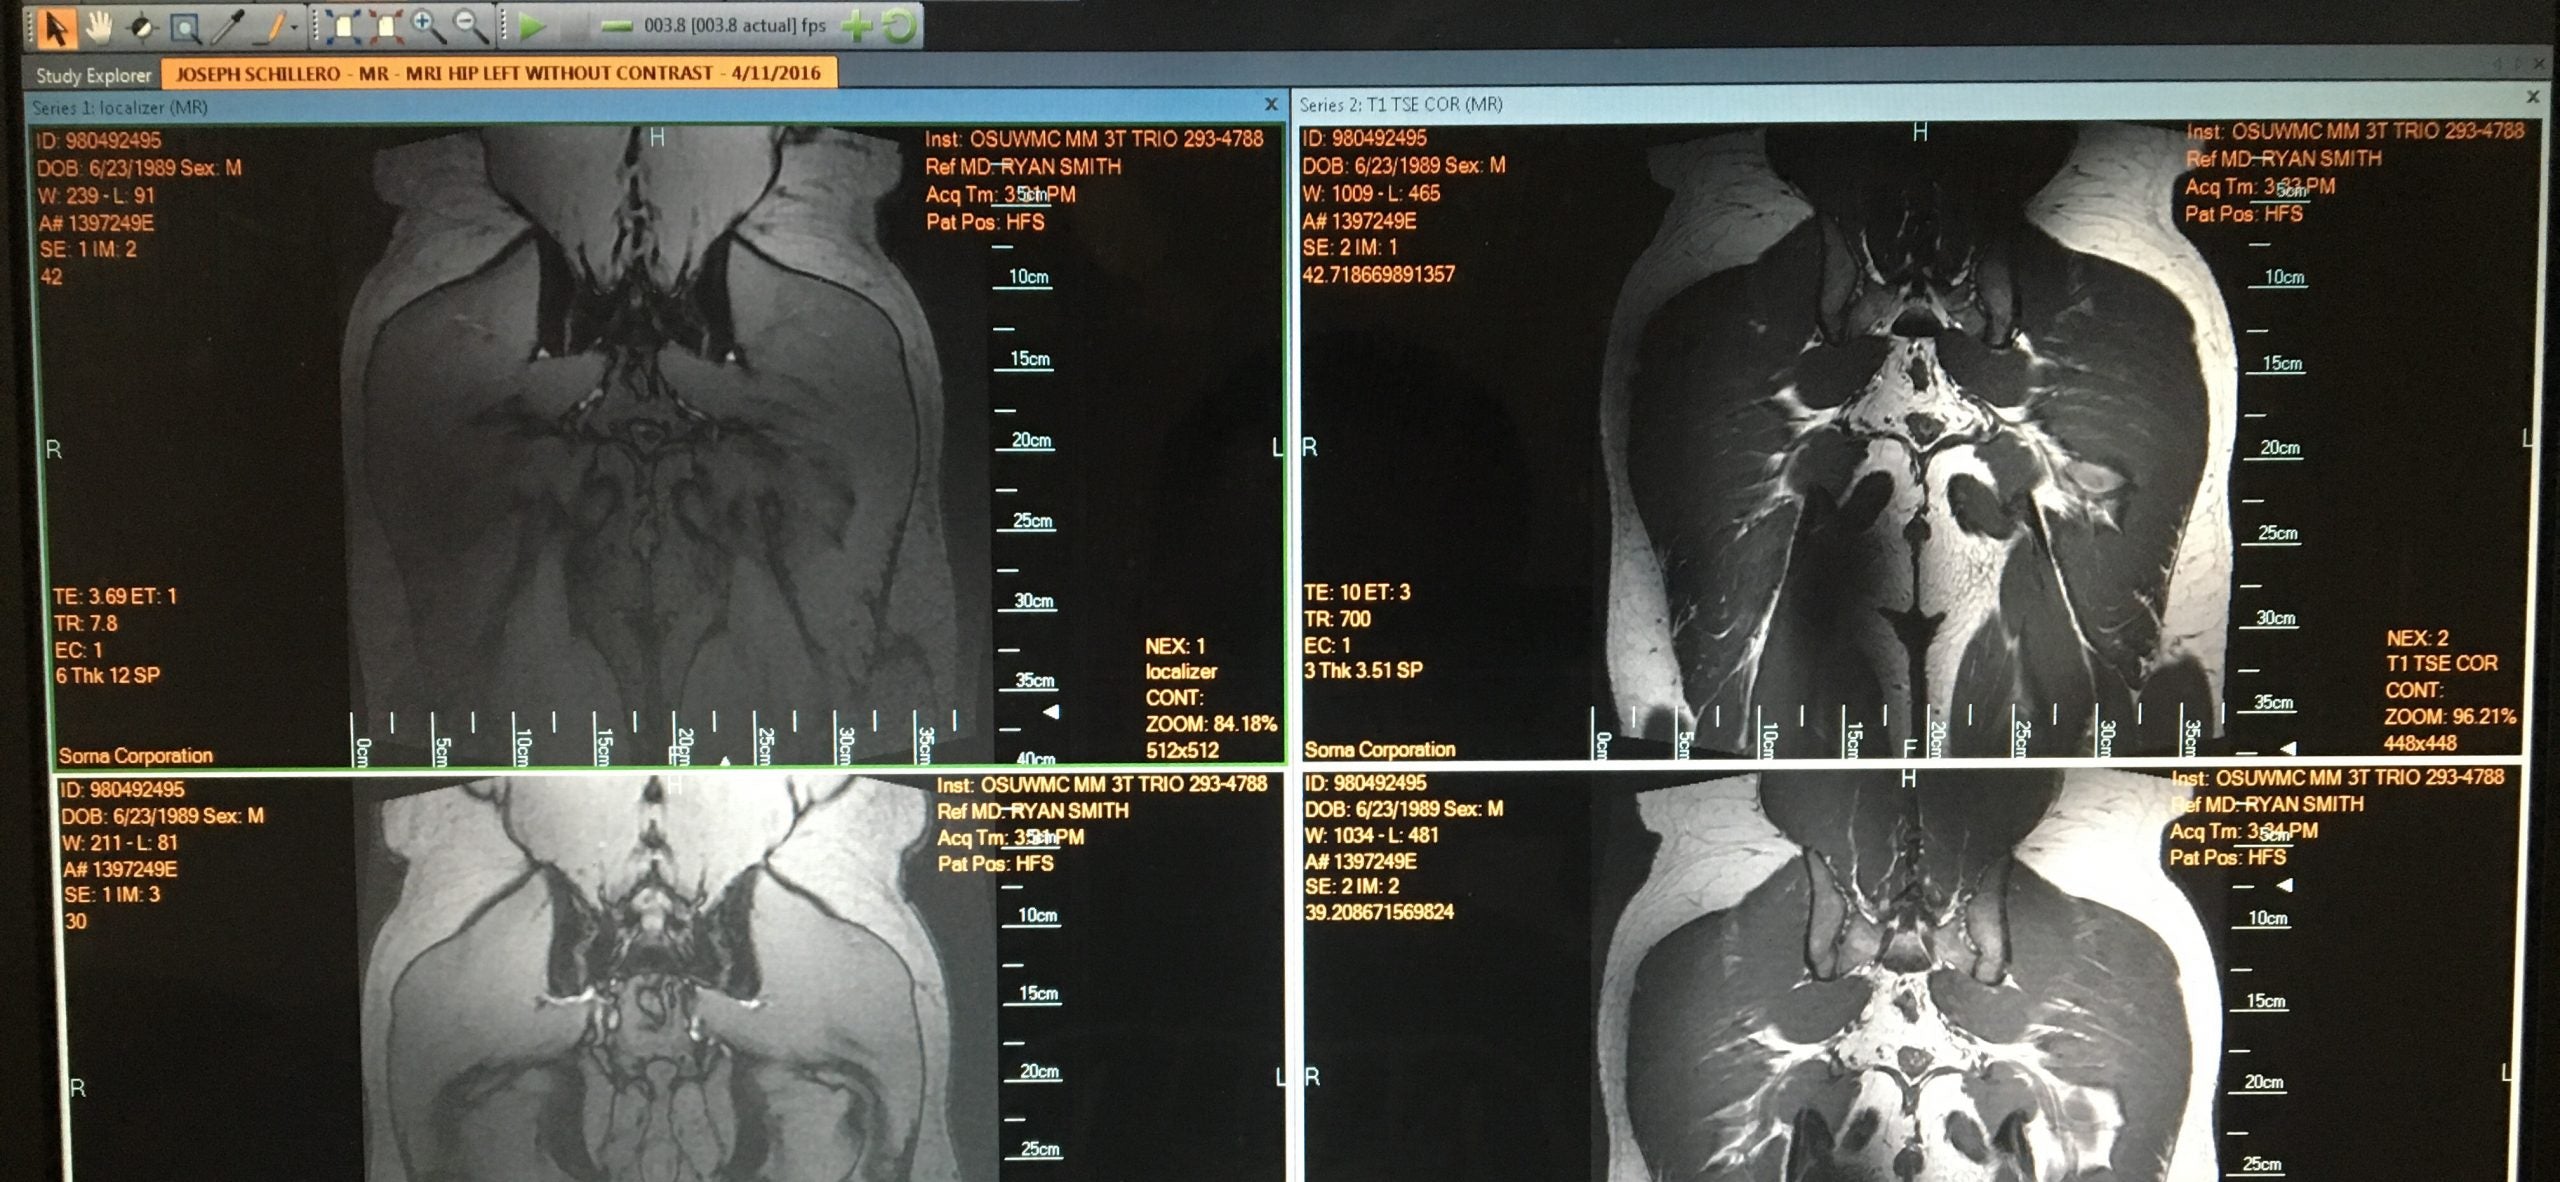

For a long time I didn't have medical insurance and neglected the doctor, but now that I have pretty good coverage with my job and the Arnold is done, I've been trying to really address the issues. I've been getting a lot of help from EliteFTS Columnist & Physical Therapist Dani Overcash, and using PRI techniques and some motor patterning stuff has helped with evening out some issues and improving my range of motion. I've also been traveling to Columbus to see Dr. Ryan Smith (who is a long-time associate of elitefts) where he's been helping me with some soft tissue work as well. Ryan recommended getting an X-Ray and MRI, and I got both, which leads us to today.. Ryan set me up with an appointment with Dr. Thomas Ellis, who specializes in hip joint conditions and works a lot with athletes. Dr. Ellis discussed my MRI/X-Ray results with me and then took me through some range of motion tests. Some of the issues from my MRI were:

Bony proliferative changes of the femoral head-neck junctions bilaterally suggestive of cam type deformities.

Small tears in both labrums (anterior-superior).

Low grade irregularity of the superior right acetabular cartilage.

Subcortical cysts along the anterior left femoral head.

Indistinctness and thickening of the ligamentum teres bilaterally suggestive of prior injury.